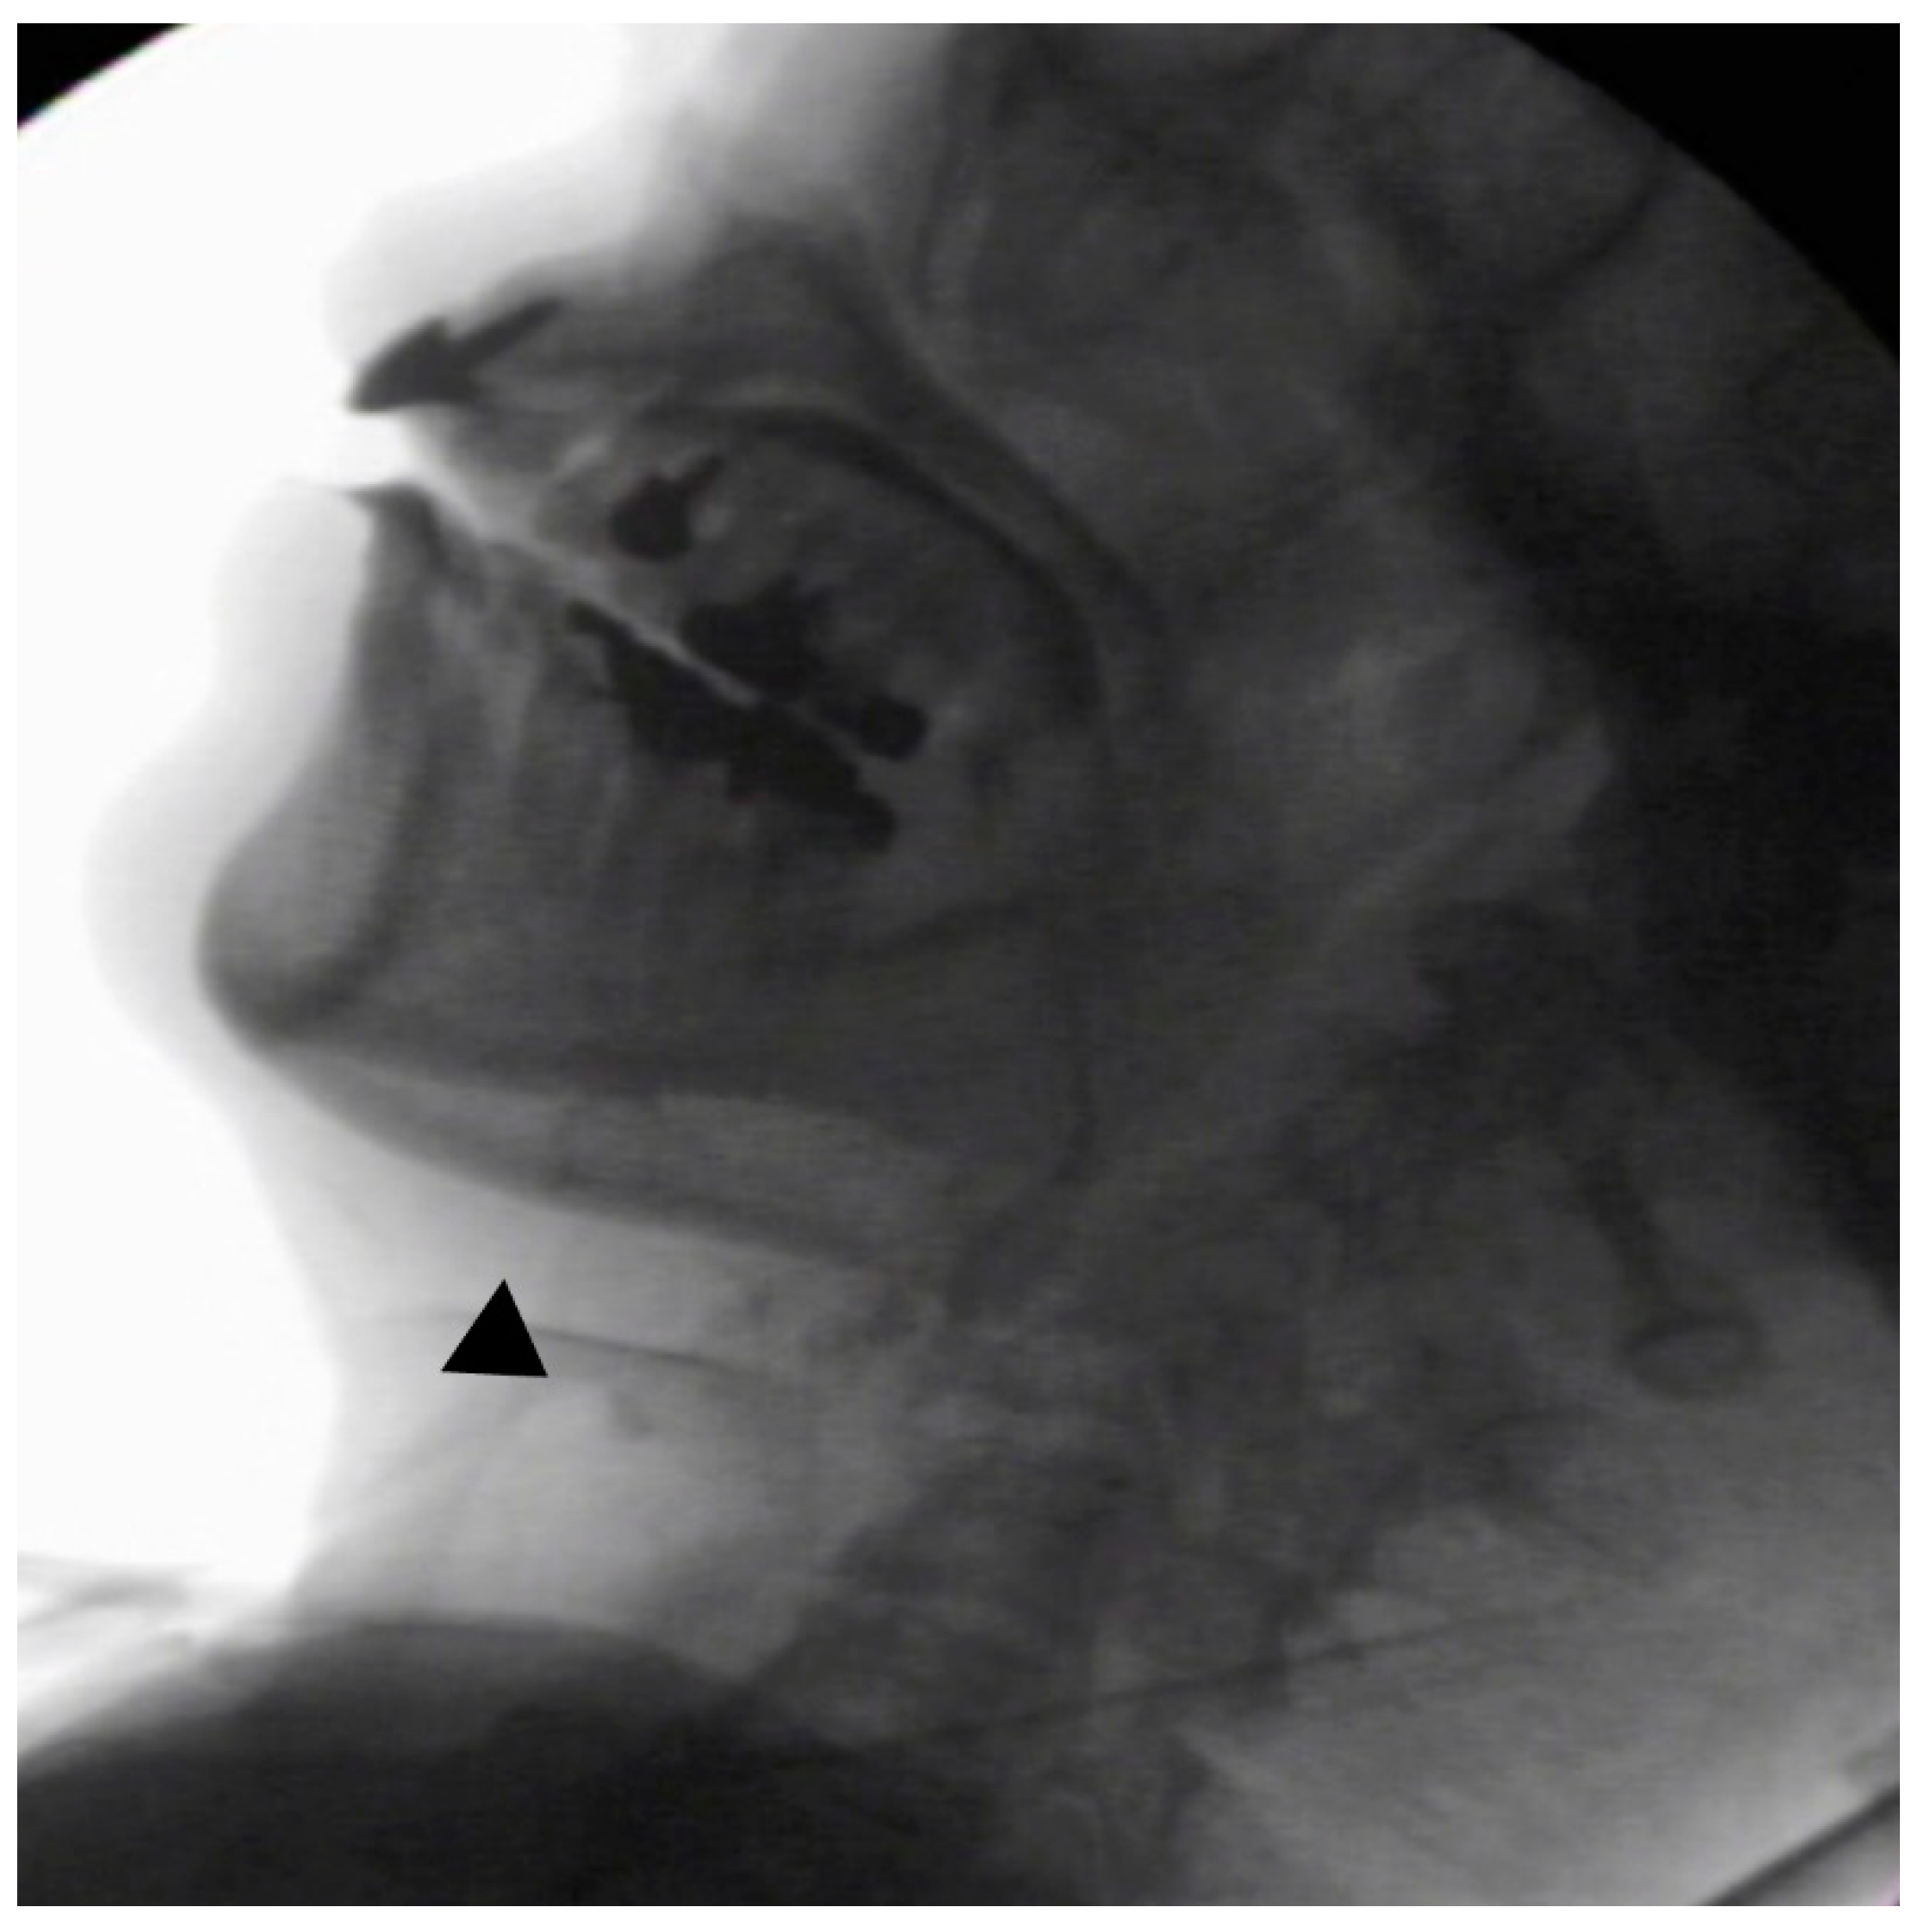

In the seated position, spoon-feeding was infeasible and bolus transport did not occur; furthermore, anterior–posterior tongue movement caused most of the food to dribble out of her mouth. After placing food on top of her tongue using a tube-fitted syringe, most still dribbled out of her mouth (Figure 1a); however, a proportion was transported into the pharynx (Figure 1b). Furthermore, after placing food at the back of her tongue with the patient reclined at 30°, a small amount still dribbled out of her mouth; however, the patient could swallow without aspiration (Figure 2). After increasing the amount placed in her mouth at one time to 7 mL, more food dribbled out of her mouth (Figure 3); additionally, there was a decreased amount transported to the pharynx. When 5 mL of a moderately thick paste was placed in her mouth, none of it dribbled out; however, slight silent aspiration was present (Figure 4). There were no particular issues observed due to peristalsis from the upper esophagus to the stomach.

Figure 2.

The patient was reclined at 30° for the administration of 5 mL of an extremely thick paste. Oral transport was better than in the sitting position; furthermore, a little of the food dribbled out of the mouth (above ▲), and no aspiration occurred (below ▲).